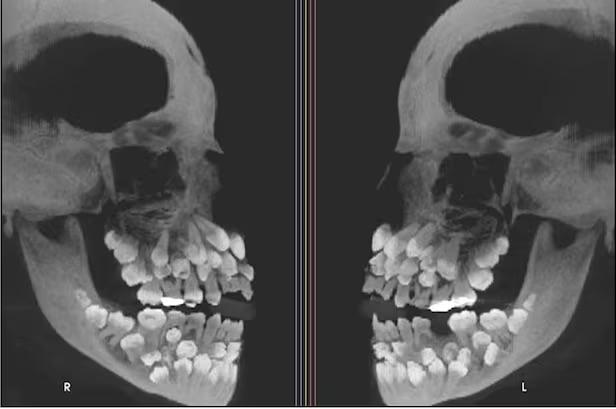

巴西傳出11歲女童牙齒多達81顆。(示意圖/資料照片)

巴西傳出一宗罕見病例,一名11歲女童日前拔牙就診,豈料牙醫為她照X光時,竟發現她竟然有多達81顆牙齒,是普通人的1倍之多,嚇壞牙醫。

綜合外媒報道,這名來自巴西米納斯吉拉斯州(Minas Gerais)的女童,因為想拔除一顆上排乳齒到醫院就診,但在拍攝X光後,醫生竟意外發現,她口中竟藏有18顆乳齒、32顆恆齒,以及31顆多生齒,總數多達81顆。

女童是非常罕見的「多生牙」病例,一般情況下,患者僅多出少量牙齒,但這名女童多出來的牙齒,數量多到驚人。醫生透過染色體檢測,發現女童的第9號染色體出現罕見變異,不過目前尚無法確認,是否直接導致牙齒異常暴增。

根據資料顯示,多生牙在亞洲人發生率約3%至5%,男性比例是女性的兩倍左右,多生牙恐引發咬合不正、牙齒萌發受阻以及囊腫等風險,需進一步評估是否拔除。